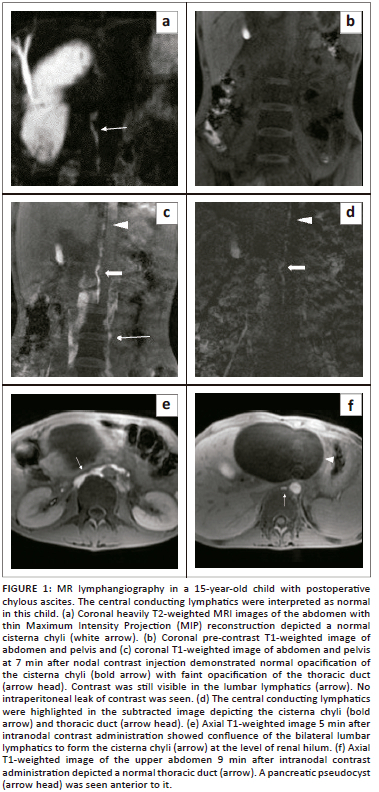

A DCE-MR lymphangiogram study was performed for the patient after intranodal gadolinium administration. A normal calibre and course of cisterna chyli was seen on coronal heavily T2-weighted images (Figure 1a). Post nodal contrast scans revealed the right and left lumbar lymphatic channels, joining to form the cisterna chyli (Figure 1e), followed by opacification of the thoracic duct on subsequent images (Figure 1c, d and f). No major duct injury was seen. There was no contrast extravasation in the peritoneal cavity.

In both presented cases, intranodal DCE-MR lymphangiography was performed. The procedure involved initial routine MRI abdomen and pelvis sequences using a 3 tesla MRI scanner along with heavily T2-weighted images for delineation of the cisterna chyli and thoracic duct. Following this, the patient was shifted outside the MRI unit for nodal cannulation under ultrasound guidance. Using an aseptic technique, 1% lidocaine was injected intradermally at the area of interest, following which, bilateral superficial inguinal lymph nodes were cannulated using a 22-gauge needle followed by saline injection. The lymph nodes became more prominent after saline injection and after ensuring adequate placement, the needle was connected to 10-cm long tubing attached at its end to a three-way stop cock. A syringe containing a gadolinium and saline solution ratio of 1:1 was connected to the stop cock. The gadolinium dosage was 0.1 mmol/kg. The patient then returned to the MRI table and a mask T1-weighted image of the chest and abdomen was obtained prior to the injection of gadolinium via the stop cock. Multiple axial and coronal post-contrast T1-weighted (VIBE) images of the abdomen followed by the chest were obtained at every 1-min interval for about 30 minutes, and subtracted images were generated to enhance the sensitivity for detecting intraperitoneal contrast leakage.

Variable findings can be seen on MR lymphangiography depending on the aetiology of chylous ascites and the level of occlusion or leak, which may involve the intestinal lymphatics, cisterna chyli or lower thoracic duct. Extravasation of contrast into the peritoneal cavity may also be seen.5 Dynamic contrast-enhanced MR lymphangiography is more sensitive than radiographic lymphangiography in establishing the site of the leak because of the lower viscosity of gadolinium-based contrast agents compared to ethiodised oil. However, in more than half of the cases, the leak site may not be established. This is because the cisterna chyli receives supply from the intestinal, hepatic and bilateral lumbar lymphatics, and it is the lumbar lymphatics that receive direct drainage from the inguinal nodes while the intestinal lymphatics are off track and distant from the site of injection.2,5 However, establishing the integrity of the central conducting lymphatics is crucial for management decisions.

In the first case, there was no evidence of injury to the cisterna chyli or thoracic duct on MR lymphangiography. As a result, surgery was performed and embolising agents were injected into the mesenteric nodes to target the distal intestinal lymphatics. In the second case there was non-opacification of the CCLs cranial to the renal hilum due to compression by enlarged abdominal lymph nodes. The patient was commenced on anti-tuberculous therapy with close monitoring and there was a gradual reduction in chylous output.